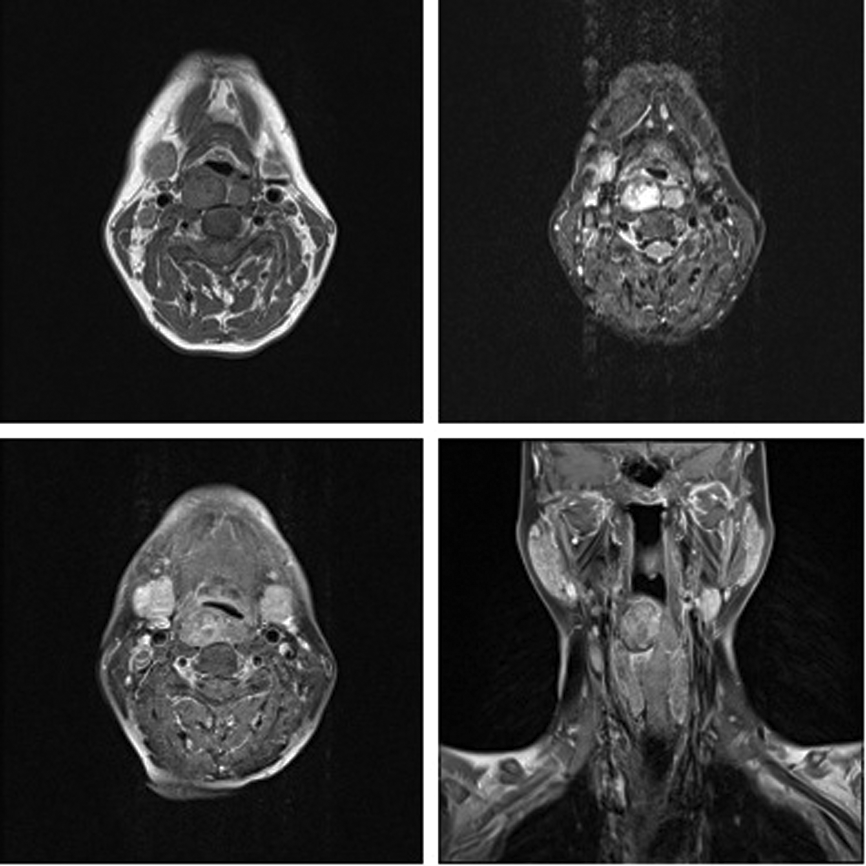

Magnetic resonance imaging (MRI), also radiation free, does not usually resolve normal parathyroid glands. Adenomas are seen as masses of low signal intensity on T1 images and high signal on T2 images with increased conspicuity following both fat suppressed imaging with short tau-wave inversion recovery imaging (STIR) and with gadolinium contrast administration (Figure 4) [6, 7], unfortunately the MRI appearance of adenomas varies according to their composition, they can be difficult to differentiate from lymph nodes and the reported sensitivity rate for localisation of parathyroid lesions with MRI is lower than SPECT scintigraph [7]. It also is worth noting that in the UK waiting times for MRI examination are prolonged relative to other imaging modalities and that the technique is not suitable for claustrophobic patients and as such MRI is not routinely used in the assessment of hyperparathyroidism.

Figure 4: MRI of the same patient as Figure 1. Unenhanced T1 (top left) demonstrates two retropharyngeal adenomas. These are more conspicuous on the STIR images (top right) and enhance following contrast administration (post contrast T1 axial bottom left and post contrast T1 coronal bottom right).